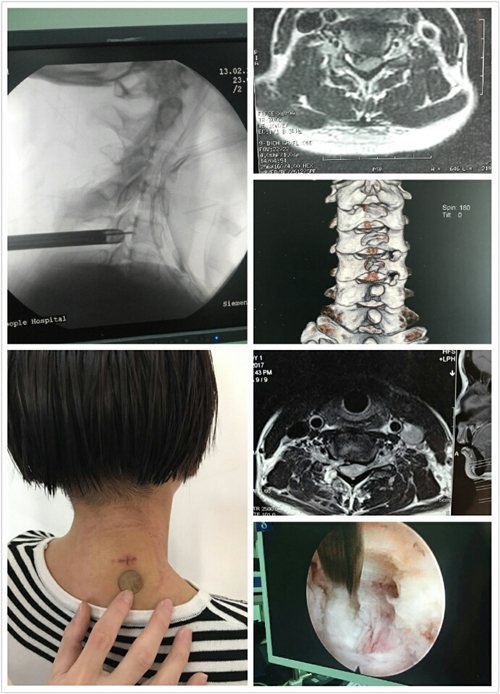

2月14日,我院第一例自主完成的颈椎间孔镜髓核摘除+椎间孔减压术成功实施。负责主刀的骨一科熊龙博士也成为了我院利用椎间孔镜治疗颈椎病的第一人!

经过细致周全的各项术前准备,2月13日下午5时50分,熊龙主任在局麻下为患者实施了颈椎间孔镜髓核摘除+椎间孔减压术。术中患者主述左上肢麻木症状明显减轻,双下肢肌力较术前也有所恢复。手术历经8个小时后成功结束,术后第二日患者便开始下床活动,目前恢复情况良好,患者及家属对手术效果表示十分满意!

据了解,该技术为脊柱微创技术的金字塔尖技术,难度非常大。目前国内仅少数几家医院开展,北上广的一些著名大医院均尚未开展。作为全院自主完成椎间孔镜治疗颈椎病的第一人,熊龙博士表示,不选择传统手术方式的原因有很多,传统手术需要开大刀放置钢板,这会使得脊柱的稳定性受影响,且较容易发生其他节段颈椎间盘的退变,一旦发生这种退变,患者则必须再次进行手术,而再次手术不仅增加病人痛苦,增加患者家庭的经济负担,同时手术的难度也加大。事实上,椎间孔镜这项微创技术已经不单纯只局限于用来治疗腰椎间盘突出,社会的不断进步加上人们健康意识的不断提高,这使得每一位外科医生都在绞尽脑汁地探索更安全有效的手术方式去治疗每一种疾病。椎间孔镜从最早治疗腰椎间盘突出到后来的椎管狭窄、异物刺入体内、脊柱结核,再到今天的治疗颈椎病,随着这项技术发展越来越成熟,必然会有更大的潜力和价值等待发掘。

与传统手术相比,椎间孔镜治疗颈椎病的优势在于:一、在局麻下操作,安全性更高;二、对人体创伤小,且不影响美观,切口仅有1cm;三、大大降低了手术费用,减轻家庭负担;四、常规手术后复发翻修手术、手术后发生颈椎相邻节段退变、神经黏连等并发症的几率大大降低了!